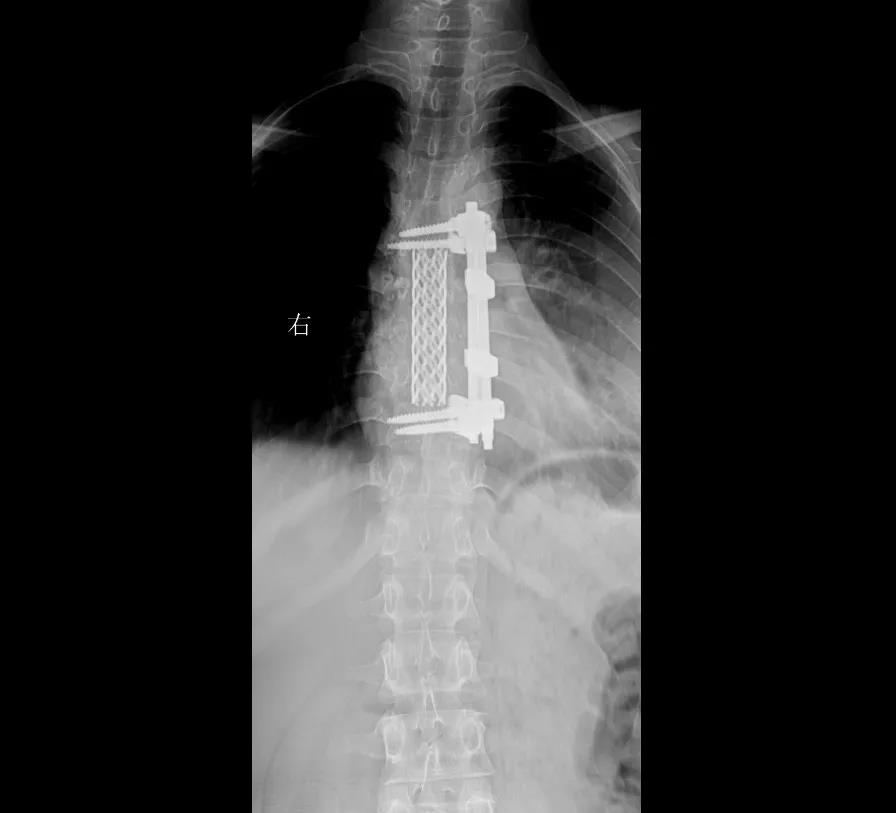

术前,黄永红带领的骨科团队进行了周密的术前规划,手术当天,骨科主任黄永红主刀,为扎西实施了经前路胸6/7/8/9椎体结核病灶清除、椎管减压、钉棒系统+取自体植骨融内固定术、胸腔闭式引流术,历时6个多小时,顺利为扎西清除脊柱结核病灶,并重建脊柱。

术后一周,扎西已经可以下地练习走路了。“我感觉腿脚的力量跟术前比要好很多,胸背痛也缓解了不少。”她开心地说到。出院时黄主任叮嘱病人:“现在手术成功了,但不能松懈下来,回去以后要继续抗结核治疗,记得定期复查!现在,扎西已经完全康复。